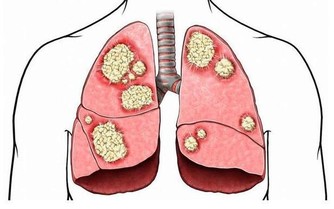

到5月初,小寶全身慢慢變黃,體重下降,還整天精神恍惚,媽媽趕緊帶他去縣醫院,一檢查發現,黃疸值已經升到128;等小寶轉到杭州治療時,黃疸指數已經高達518。

目前小寶已經接受了兩次人工肝治療,雖然病情有所好轉,但依然需要密切觀察。